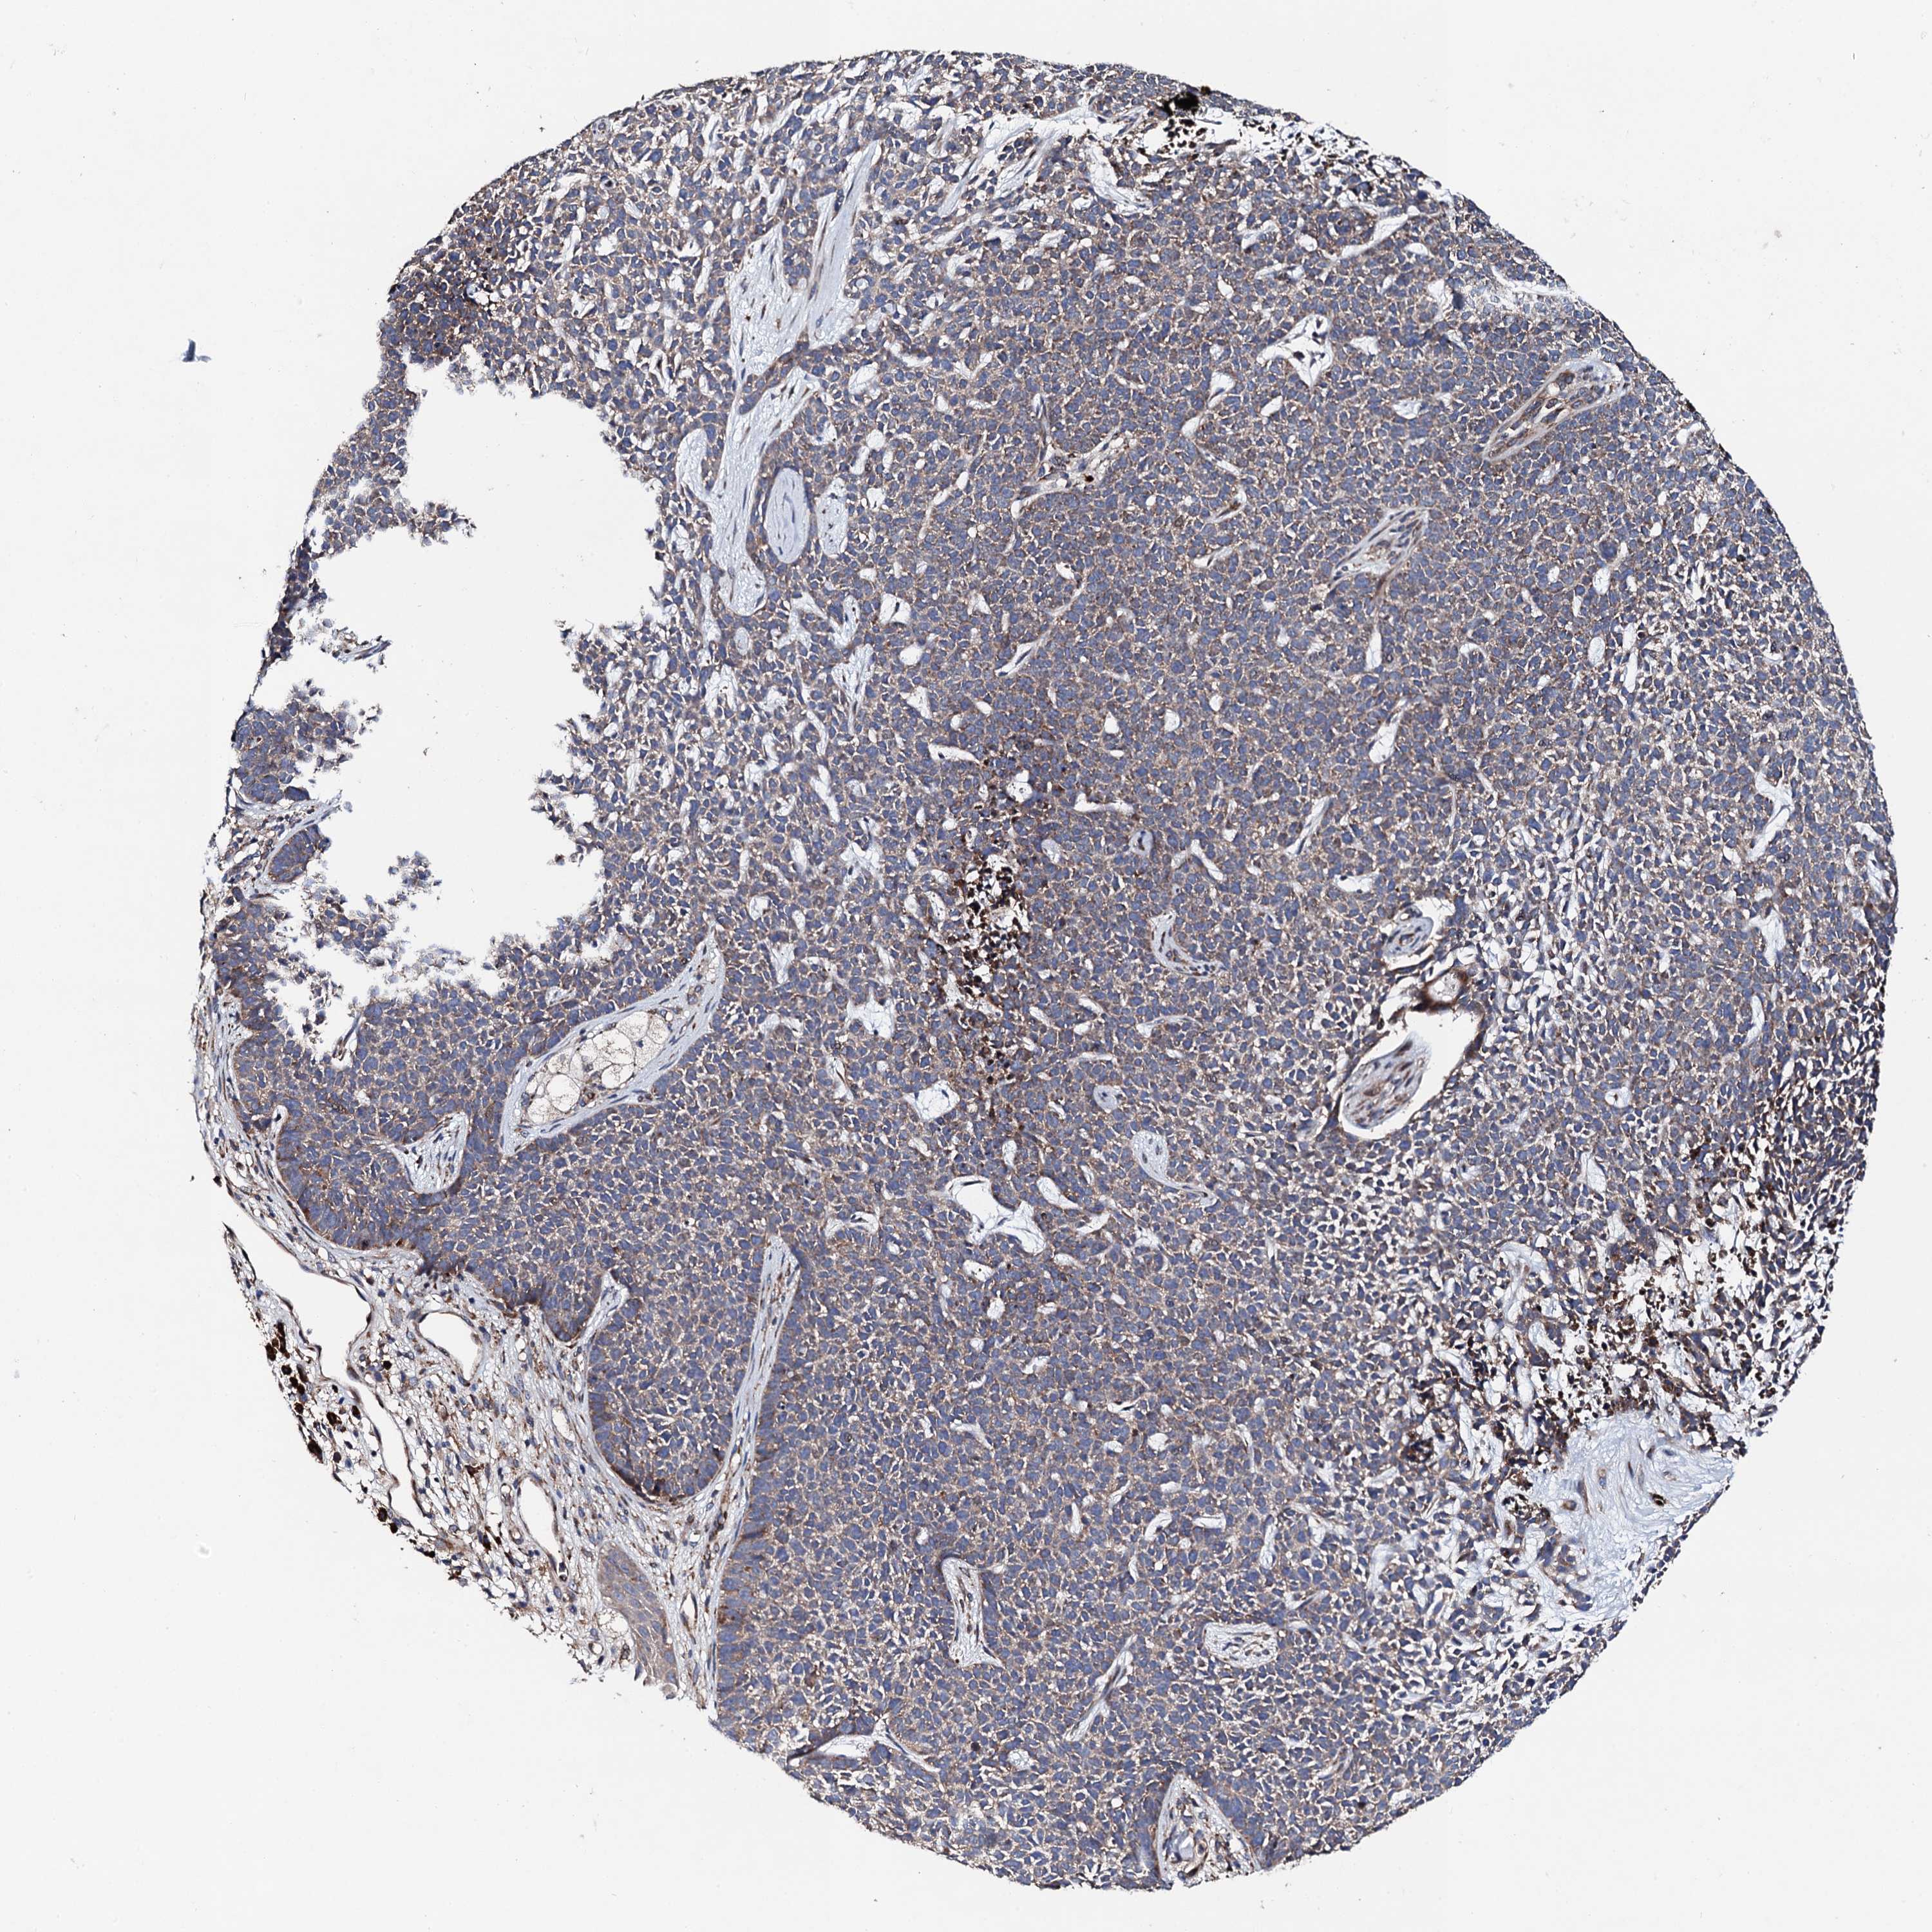

SKIN CANCER - Protein expressioni

A mouse-over function shows sample information and annotation data. Click on an image to view it in a full screen mode. Samples can be filtered based on level of antibody staining by selecting one or several of the following categories: high, medium, low and not detected. The assay and annotation is described here.

Antibody stainingi

Antibody staining in the annotated cell types in the current human tissue is reported as not detected, low, medium, or high, based on conventional immunohistochemistry profiling in selected tissues. This score is based on the combination of the staining intensity and fraction of stained cells.

Each image is clickable and will lead to virtual microscopy that enables deeper exploration of all samples and also displays staining intensity scores, fraction scores and subcellular localization as well as patient and tissue information for each sample.

Antibody HPA040249

Basal cell carcinoma

Squamous cell carcinoma, NOS

Squamous cell carcinoma, metastatic, NOS